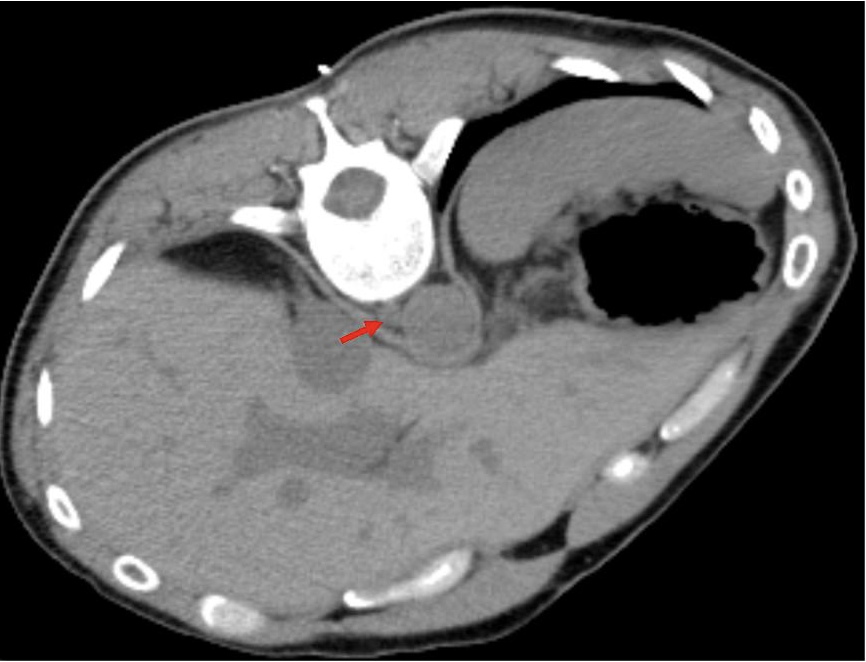

The location proved a challenge for access (Figure 1). The lesion was nestled anterior to the vertebral bone, and posterior to the liver and the aorta. There were no traditional percutaneous approaches that would guarantee access while maintaining safety. After a multidisciplinary discussion between medical oncology, radiation oncology, and interventional radiology, the decision was made to pursue a left transpedicular, transvertebral body approach. A biopsy would be performed and, if immediate assessment of the biopsy was positive for malignancy, cryoablation in the same session for immediate local tumor control.

FIGURE 2. Initial axial noncontrast CT image from day of procedure. A red arrow points to the right retrocrural lymph node lesion, nestled anterior to the vertebral bone, and posterior to the aorta and liver.